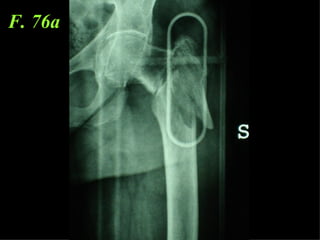

F. 76a

La placca a compressione percutanea (PC.C.P.) di Gotfried è un mezzo di sintesi studiato per assicurare un “impattamento controllato” delle fratture pertrocanteriche grazie alle due viti telescopiche prossimali che garantiscono una ottima stabilità rotazionale

Con la placca di Gotfried non si è mai riscontrato un danno iatrogeno del muro laterale e nessun collasso della frattura.Ciò è dovuto al fatto che i fori per l’applicazione delle due viti prossimali sono di piccolo diametro (9 mm) rispetto ai 16-32 mm necessari per introdurre la vite cefalica di un chiodo endomidollare o di una vite-placca a compressione.

La placca PC.C.P. viene inoltre applicata per via percutanea attraverso due piccole incisioni ottenendo in tal modo un minimo trauma chirurgico ed una  perdita di sangue estremamente ridotta in pazienti che per l’età  sono già in condizioni  critiche

Dal Gennaio 2005 ad Agosto 2006 110  placche di Gotfried Età media  : 78 anni (range 29-94) Tempo chirurgico: 30 minuti (range 12-45) IMMEDIATA CONCESSIONE DEL CARICO